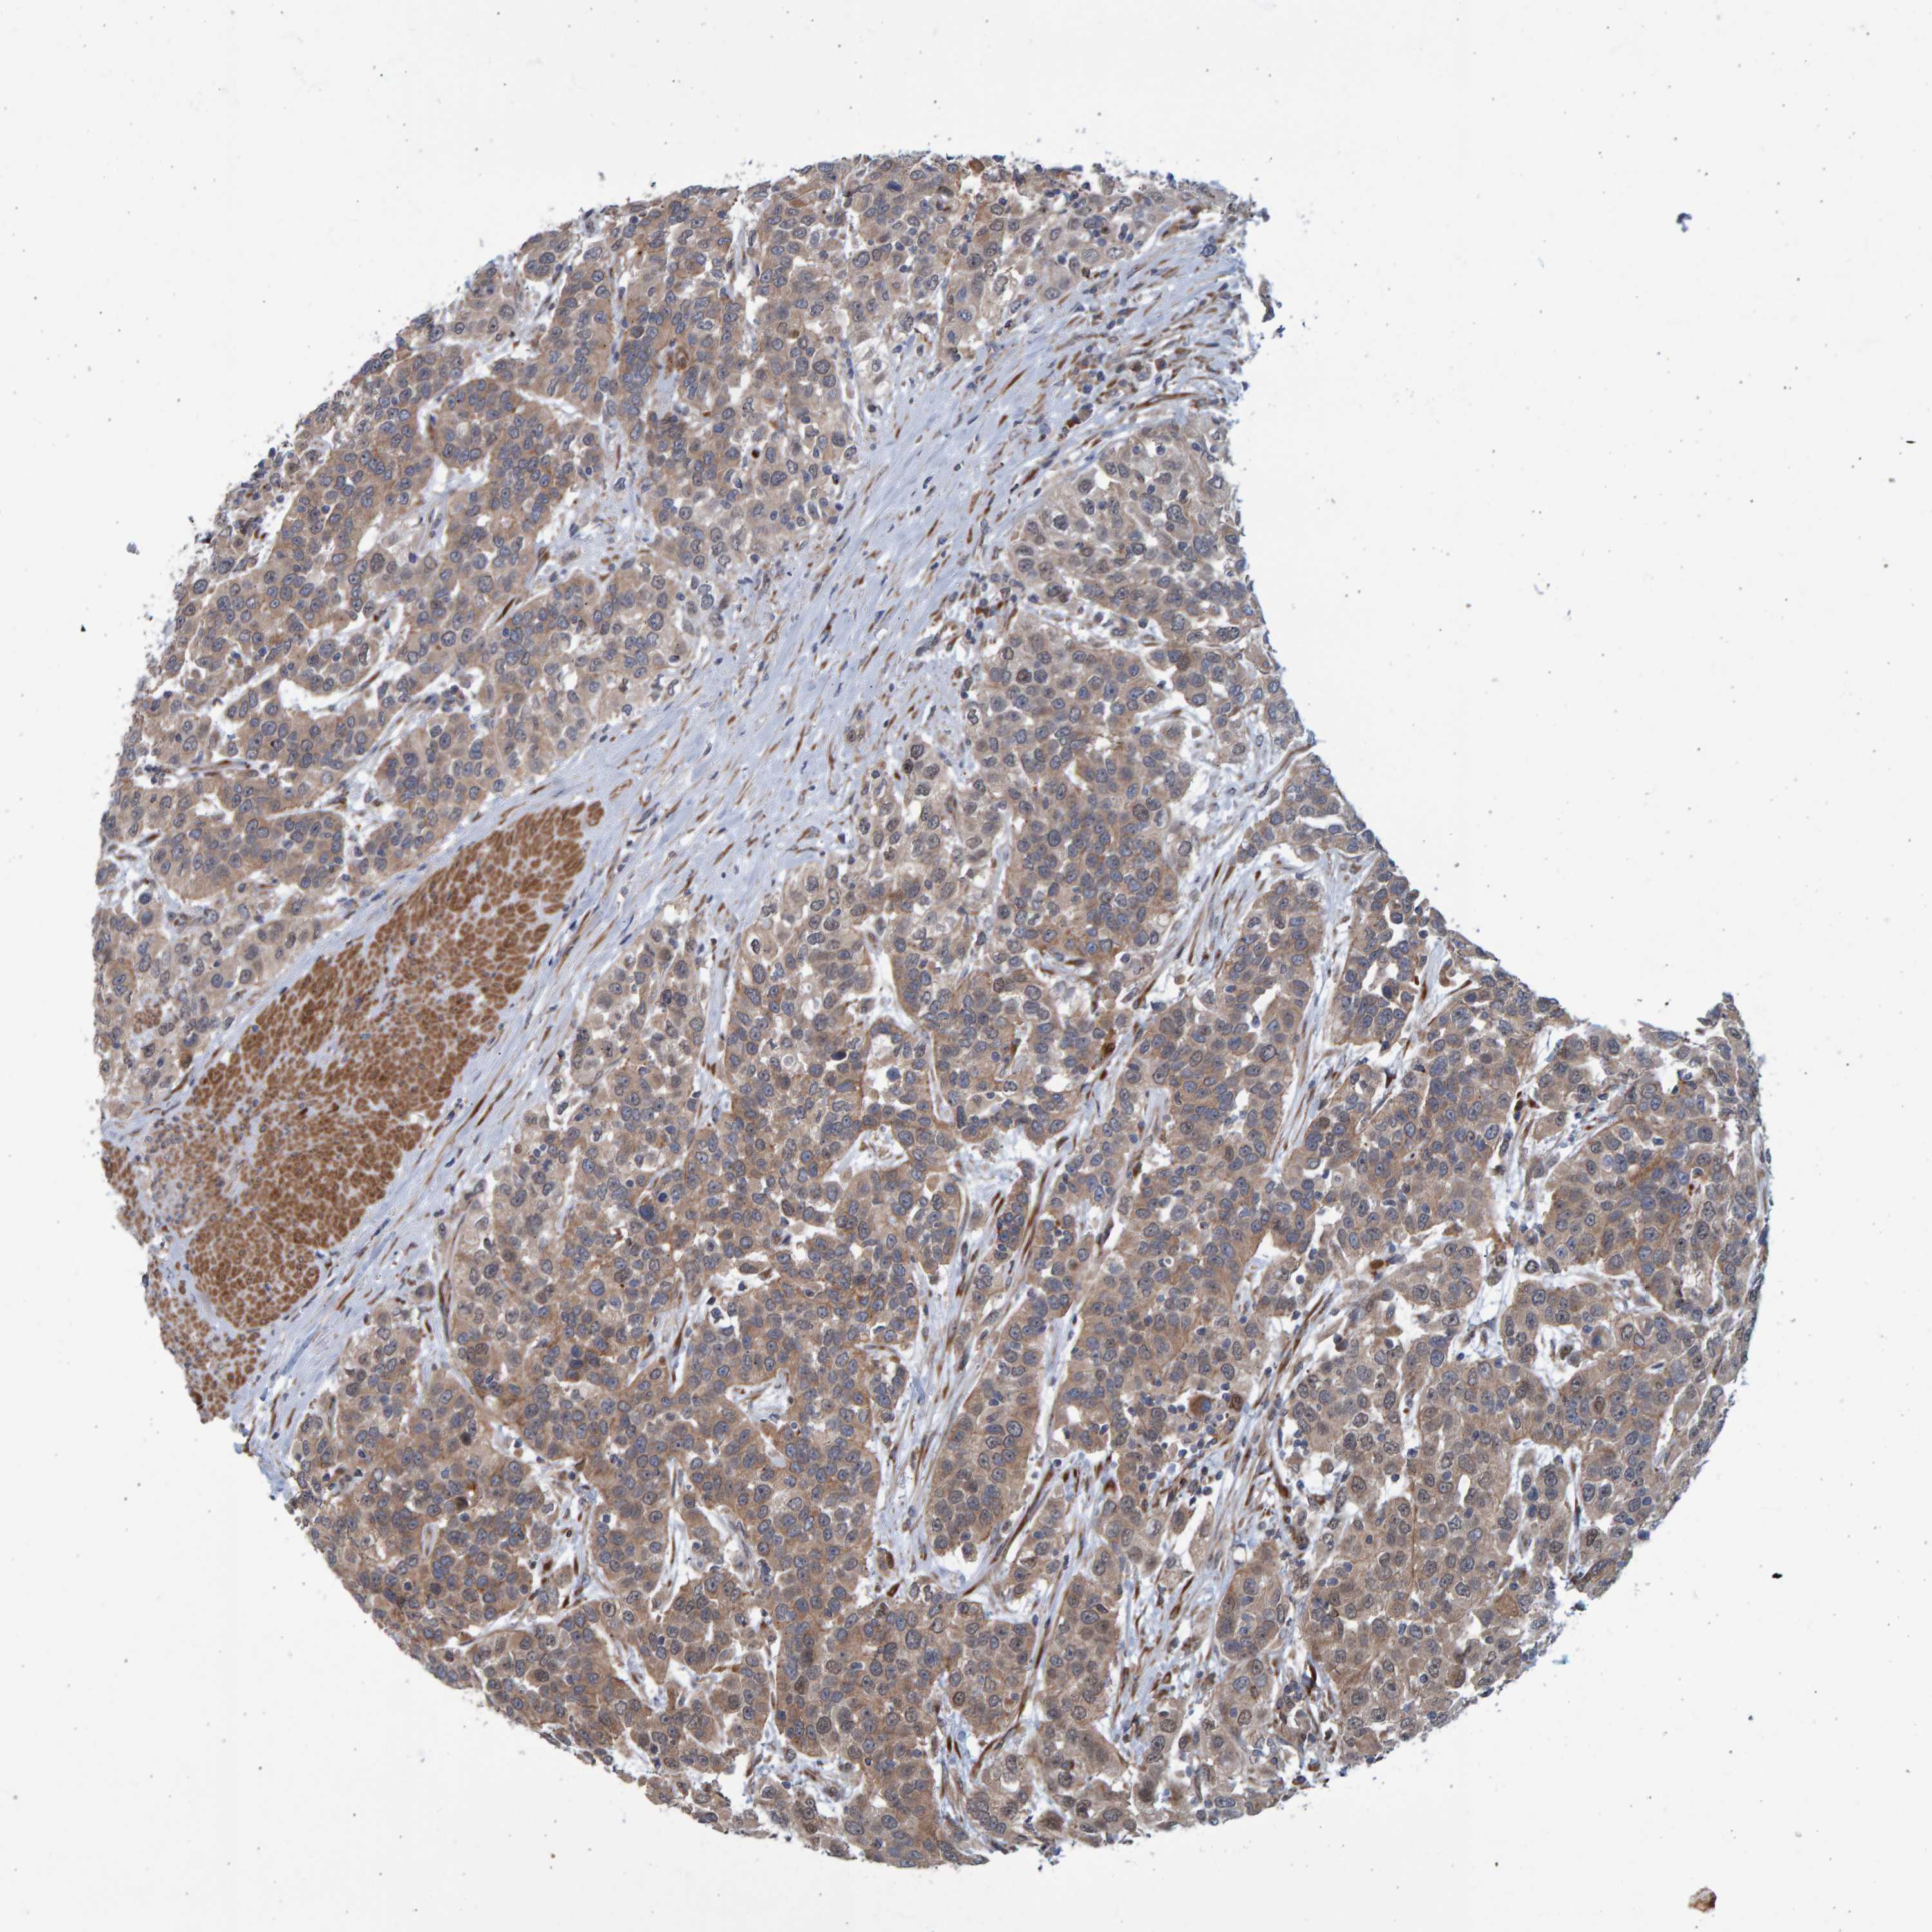

UROTHELIAL CANCER - Protein expressioni

A mouse-over function shows sample information and annotation data. Click on an image to view it in a full screen mode. Samples can be filtered based on level of antibody staining by selecting one or several of the following categories: high, medium, low and not detected. The assay and annotation is described here.

Antibody stainingi

Antibody staining in the annotated cell types in the current human tissue is reported as not detected, low, medium, or high, based on conventional immunohistochemistry profiling in selected tissues. This score is based on the combination of the staining intensity and fraction of stained cells.

Each image is clickable and will lead to virtual microscopy that enables deeper exploration of all samples and also displays staining intensity scores, fraction scores and subcellular localization as well as patient and tissue information for each sample.

Antibody HPA019366

Urothelial carcinoma, Low grade

Urothelial carcinoma, High grade